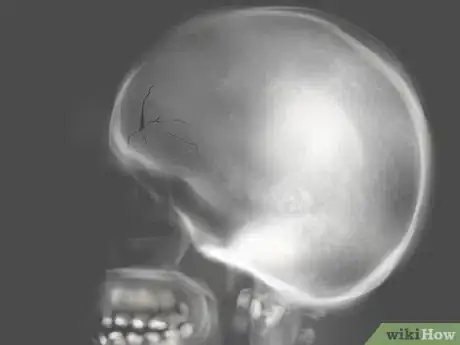

2Check for broken or fractured bones. If you have received a hard blow to the face, be sure that you do not have any breaks or fractures under the skin. This is especially important if a cut is due to a car accident or any very forceful hit.[11]